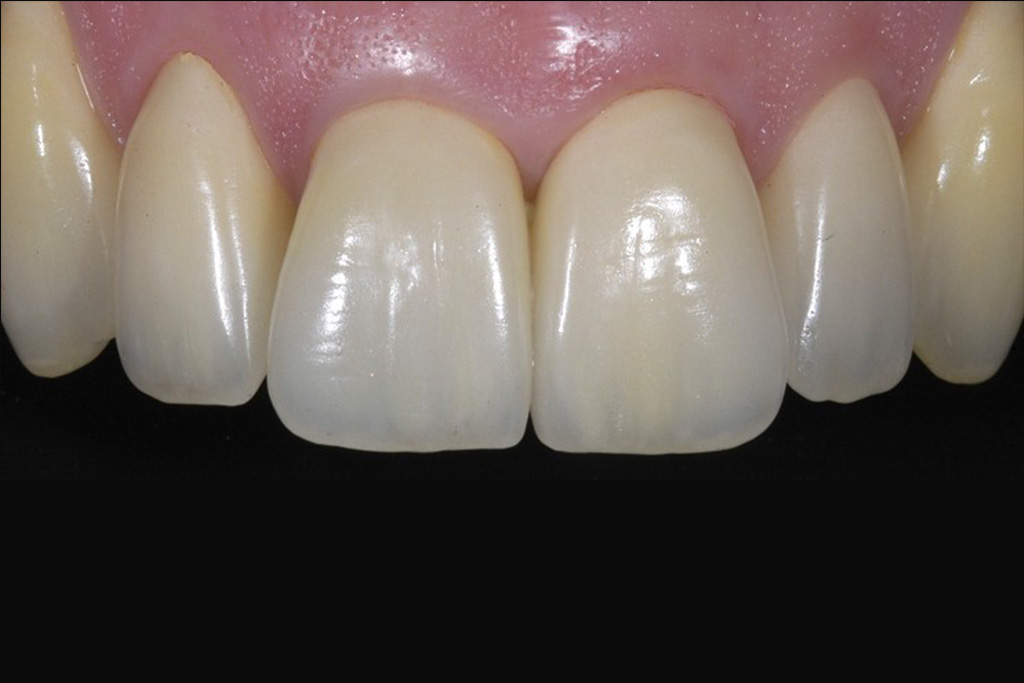

Die präzise Darstellung präparierter Zahnstümpfe auf dem zahntechnischen Meistermodell stellt auch heute noch eine der wichtigsten Schnittstellen zwischen Zahnarzt und Zahntechniker dar. In der Produktionskette hin zur fertigen Krone nimmt dabei der Zahnarzt eine entscheidende Schlüsselstellung ein. Nur er kann durch seine reproduzierbare und präzise Abformmethodik die Voraussetzung für ein perfektes Modell schaffen und damit Passungenauigkeiten der anzufertigenden Krone vermeiden. Dies ist besonders deshalb wichtig, weil Passungenauigkeiten an Kronenrestaurationen (Über- und Unterextension des Kronenrandes, übergroßer Randspalt ) häufig eine Fülle perioprothetischer und ästhetischer Probleme verursachen (Abb.1 ) :

Der Laser verdampft punktuell störende Gewebeanteile im Sulkus und stoppt gleichzeitig durch seine blutungsstillende Wirkung die Gewebeblutung . Dabei ist die Gewebeschädigung (=Trauma) minimal. Durch diese minimaltraumatisierende Wirkung ist die anschließende Wundheilung wesentlich schmerzärmer als bei der früher üblichen elektrochirurgischen Abtragung. Im Zuge der Heilung ist die Schrumpfungstendenz des Zahnfleischrandes zudem erheblich geringer. Dies fördert das ästhetische Erscheinungsbild der eingegliederten Krone im Zahnhalsbereich, da der Kronenrandbereich unterhalb des Zahnfleischrandes verbleibt (Abb. 3 ).

im Bereich der Vollkeramikkronen an den Oberkieferfrontzähnen 13-23